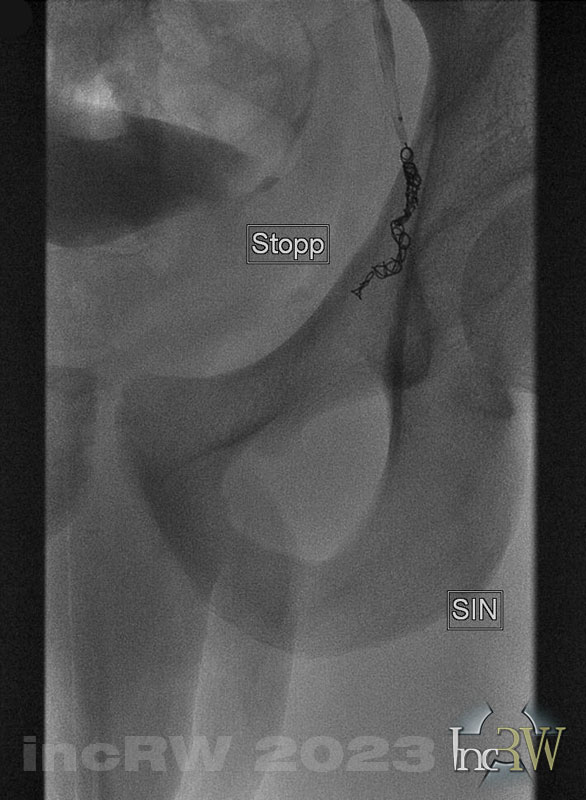

Spermatica efter coils Punktion av hö ljumskven med 5F introducer.

- I första hand läggs coils av någon modell (Concerto).

Läggs med bäst resultat i en krök eller sväng med distala coil-änden förankrad mer distalt för att minska risken för migrering. - Avvakta några minuter innan kontroll med kontrastinjektion göres ifall blodavflöde passerar emboliseringsplatsen då patienten återigen får krysta.

- Ev behöver man även lägga coils i ytterligare grenar på v.spermatika som går ner mot pungen.